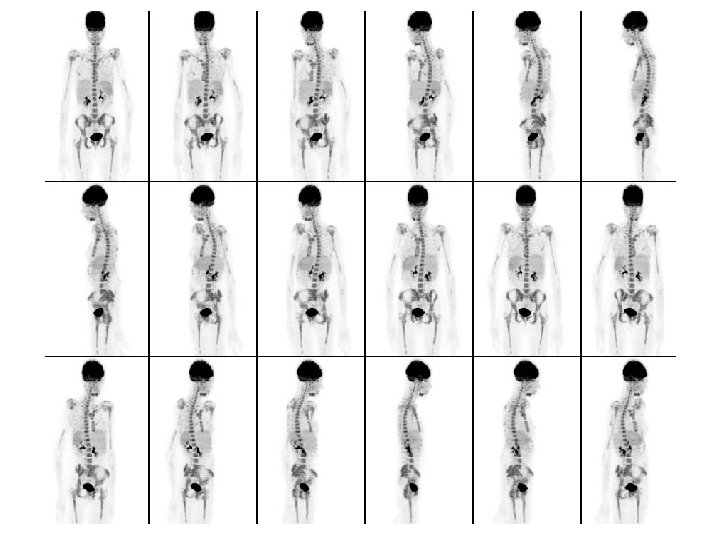

Mieloma Múltiple Diferentes patrones de captación por PET: Afectación difusa y homogénea compatible con infiltración M. O (bx: 20 -50%) (> al hígado)

NHC: 14251465 Afectación ósea poliostótica + medular

NHC: 426386 Afectación extra-medular